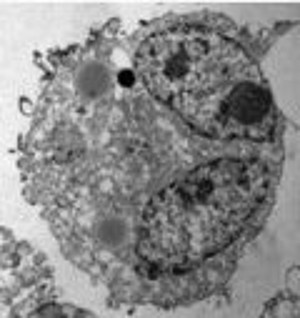

![]() | Tumorimmuntherapie beim Nebennierenrinden-Karzinom Arbeitsgruppe Univ.- Prof. Dr. med. M. Schott |